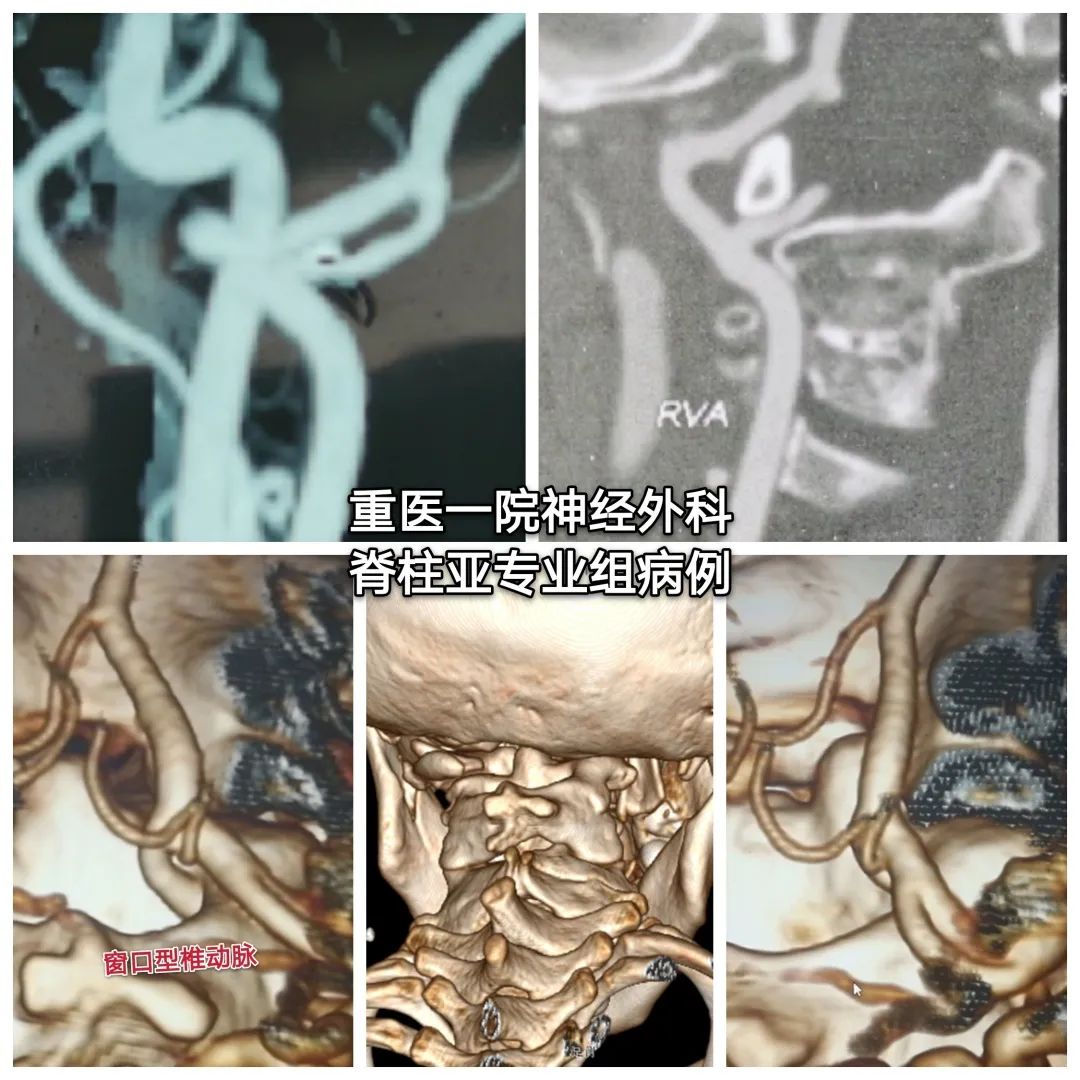

◆术前颈椎CT

寰椎右份缺如,与颈2、3椎体融合,颈4-6椎融合。

右椎动脉粗大,于颅颈部呈窗型(分3只血管后融合,其中一血管走行寰枢椎连接部间)

颅颈畸形(寰椎右份缺如、颈2/3、4-6锥体融合)